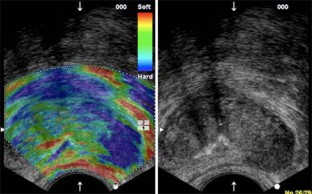

New ultrasound technologies, including color- and power Doppler ultrasound, contrast enhanced US and real-time sonoelastography have shown to improve prostate cancer diagnosis.

Contrast-enhanced ultrasound has shown a sensitivity of 100% (95% CI, 95%), a negative predictive value (NPV) of 99.8% and a positive predictive value (PPV) of 88.8% for prostate cancer detection. Real-time sonoelastography has shown a sensitivity of 86%, a specificity of 81% and NPV of 91% for prostate cancer diagnosis.

Most studies show that these new ultrasound modalities demonstrate a 1.5 to 2.5 times higher detection of prostate cancer per biopsy specimen compared with systematic biopsy. Multicenter studies results are at present lacking but are, however ongoing.

In patients with suspected prostate cancer (elevated PSA, suspicious DRE) these new ultrasound techniques should be used. These techniques can detect prostate cancer and allow a targeted biopsy approach.

• Sonoelastographie

• Elastography